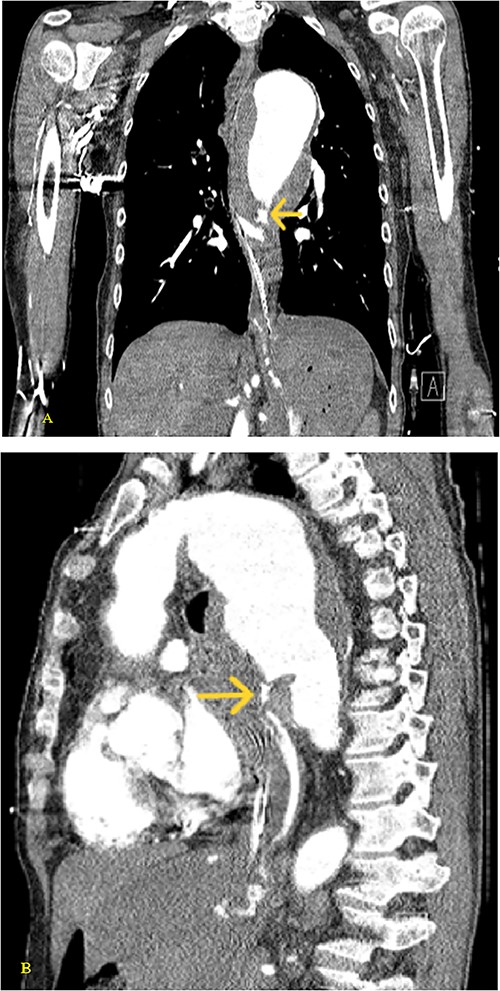

(A) Coronal and (B) sagittal views of the arterial phase CT chest with IV contrast performed during the initial trauma evaluation show aneurysmal dilation of the thoracic aorta with contrast extravasation into the esophagus and stomach.